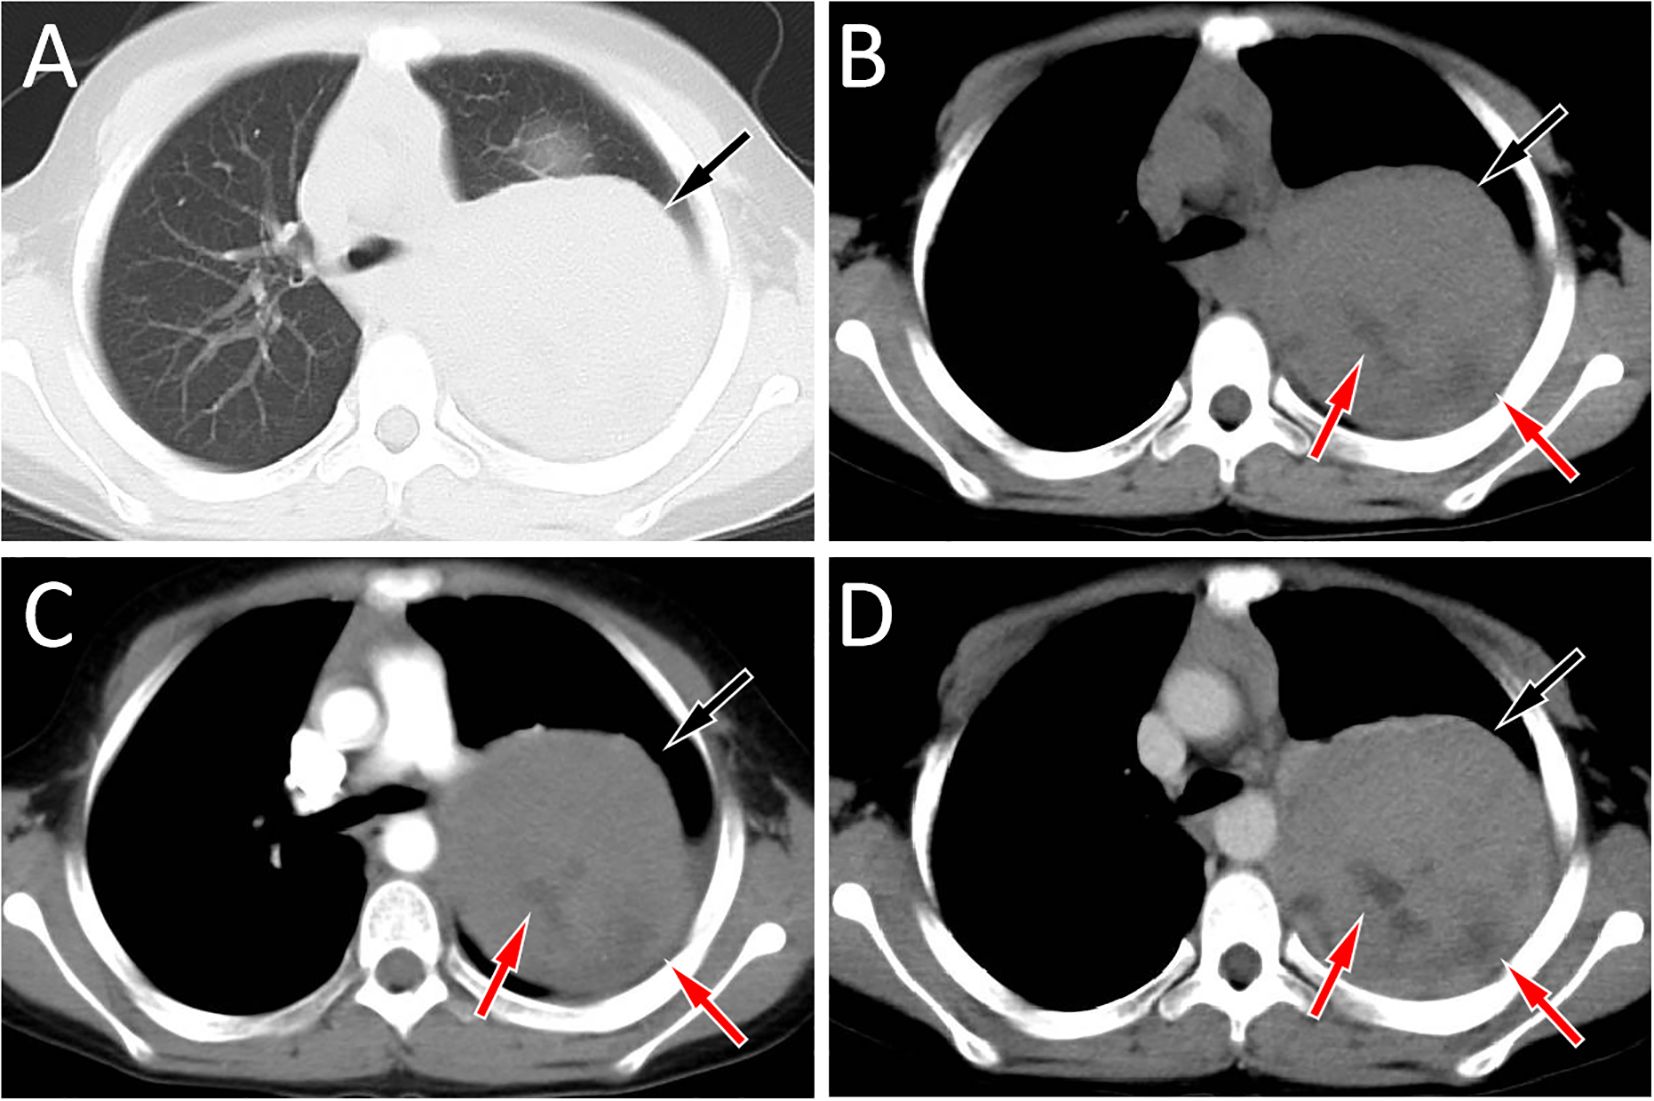

Extraskeletal Ewing sarcoma (EES) is a malignant tumor that arises in soft tissues outside the skeleton. It commonly involves the paravertebral regions, the lower extremities, and the chest wall, with mediastinal involvement being less frequent. Here, we report an 11-year-old male with pathologically confirmed EES occurring in the mediastinum. Chest computed tomography (CT) showed a large soft tissue density mass on his left posterior mediastinum, containing internal low-density cystic necrotic areas. The solid component was isointense to muscle on T1-weighted imaging (T1WI) and mildly hyperintense on T2-weighted imaging (T2WI), whereas the cystic components were hyperintense on T2WI and variably hyperintense on T1WI. On contrast-enhanced CT and T1WI, the mass demonstrated heterogeneous, progressive enhancement, suggesting the possibility of malignant tumor. A needle biopsy confirmed the diagnosis of EES. After diagnosis, the patient received systemic chemotherapy followed by surgical resection of the tumor. We also conducted a systematic review of the published literature on mediastinal EES, summarizing its clinical and imaging features, with the aim of increasing understanding of this rare disease.